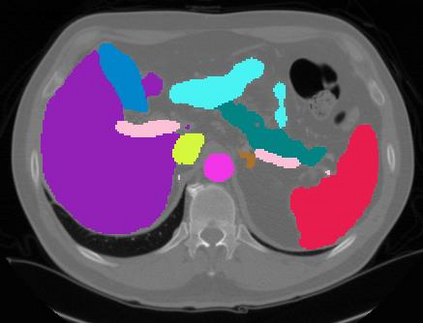

Vision transformers, with their ability to more efficiently model long-range context, have demonstrated impressive accuracy gains in several computer vision and medical image analysis tasks including segmentation. However, such methods need large labeled datasets for training, which is hard to obtain for medical image analysis. Self-supervised learning (SSL) has demonstrated success in medical image segmentation using convolutional networks. In this work, we developed a \underline{s}elf-distillation learning with \underline{m}asked \underline{i}mage modeling method to perform SSL for vision \underline{t}ransformers (SMIT) applied to 3D multi-organ segmentation from CT and MRI. Our contribution is a dense pixel-wise regression within masked patches called masked image prediction, which we combined with masked patch token distillation as pretext task to pre-train vision transformers. We show our approach is more accurate and requires fewer fine tuning datasets than other pretext tasks. Unlike prior medical image methods, which typically used image sets arising from disease sites and imaging modalities corresponding to the target tasks, we used 3,643 CT scans (602,708 images) arising from head and neck, lung, and kidney cancers as well as COVID-19 for pre-training and applied it to abdominal organs segmentation from MRI pancreatic cancer patients as well as publicly available 13 different abdominal organs segmentation from CT. Our method showed clear accuracy improvement (average DSC of 0.875 from MRI and 0.878 from CT) with reduced requirement for fine-tuning datasets over commonly used pretext tasks. Extensive comparisons against multiple current SSL methods were done. Code will be made available upon acceptance for publication.